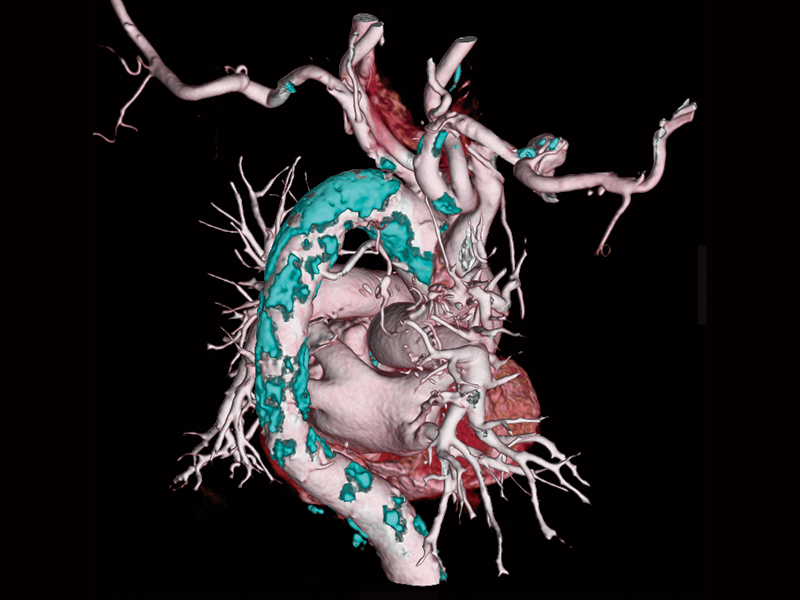

High-speed imaging(180 mm/sec)

Renal cell carcinoma(80 kV)

Intraoperative oxygen desaturation(Left)